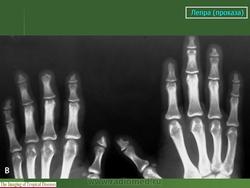

Рентгенологически специфические лепрозные оститы наблюдаются в виде (рис. 215) рассеянных множественных изолированных друг от друга очагов разрушения в корковом и преимущественно губчатом веществе эпифизарных и метафизарных концов фаланг, пястных и плюсневых костей. Реже они гнездятся в диафизах. Это резко очерченные округлые или чаще овальные просветления на месте рассасывания костной ткани бациллонесущей гранулойатозной тканью. Величина очагов в губчатом веществе колеблется от 2 до 8 мм в наибольшем длиннике, в корковом же веществе просветления меньше - до 3 мм в диаметре. Характерны весьма четкие контуры, окаймляющие костные изъяны.